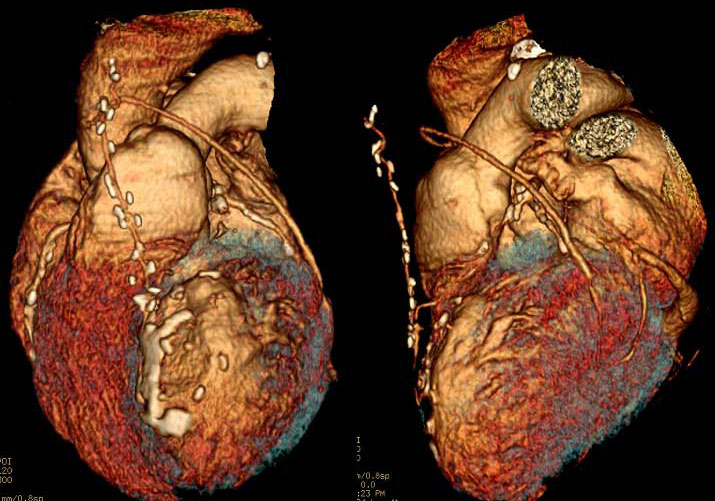

Широкое внедрение цифровых технологий в методы лучевой диагностики качественно и информационно изменили изображения исследуемых органов. Таким образом, получили широкое распространение методы трехмерного (объемного) получения и отображения данных медицинской визуализации. КТ стала первым методом, с помощью которого удалось создавать трехмерные реконструкции внутренних органов. Но теперь трехмерная визуализация возможна с помощью УЗИ, МРТ, рентгенографии, ангиографии и радионуклидных методов – т.е. всего спектра современных методов диагностики (Рис.2, Рис.3, Рис.4) [7, 10, 11]. В ближайшем будущем все исследования будут визуализироваться в виде трехмерного изображения, что является крайне важным для врачей.